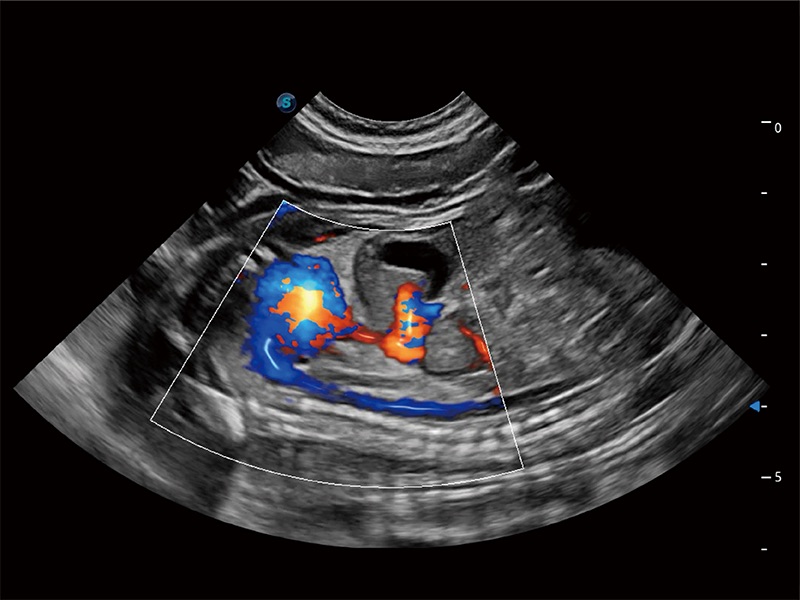

Ausgestattet mit dem gesamten Sortiment an Phased-Array-Schallköpfen von SonoScape (S1-5, 7P-A, 8P1), hochentwickelter Verarbeitungstechnologie und modernsten kardiologischen Tools bietet die ProPet-Serie Tierärzten eine umfassende ABklärung der Herz- und Myokardfunktionen.

Deckt zahlreiche Anwendungsbereiche ab, beispielsweise Reproduktion, Herz und Bewegungsapparat, und bietet die notwendigen Werkzeuge für die Bedürfnisse des Anwenders, einschließlich tierartspezifischer Formeln wie Cornell und Körperoberfläche.